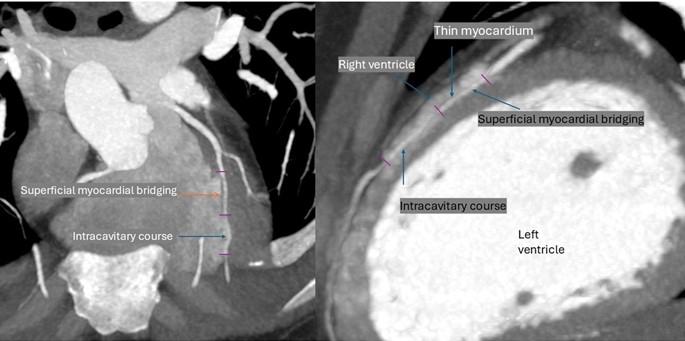

Case Summary: A female in her 30s presented with left-sided chest pain radiating to the left upper limb. ECG, echocardiography, and chest x-ray were normal. Given her age, non-smoking status, and angina-like presentation, she was referred for CT coronary angiography to look for any structural cardiac or coronary anomaly. CT showed no hemodynamically significant plaque. However, a variant course of LAD was noted, with 12 mm long and 1-2 mm deep MB affecting the mid-segment of LAD. MB continued as IC for 17 mm length along the mid-to-distal course of LAD in the right ventricular cavity between the free and septal walls of the chamber. Long-segment mild-to-moderate stenosis was noted in the affected segments (MB and IC) on diastolic reconstruction with mild pre- and post-stenotic dilatation of LAD.

IC is difficult to recognize in conventional angiography. We noticed two important imaging features in this case that can act as clues for the identification of this variant on conventional angiography. One was a subtle secondary curve noted at the level of IC. The other was a relatively posterior position of LAD with respect to the great cerebral vein and a demonstrable increased distance between them. The patient was managed medically and counseled in cardiology.

Discussion: MB and IC are often labeled as benign conditions.MB is an important differential in young, non-smoking patients who are at low risk of developing atherosclerosis. It can present with angina-like chest pain, acute coronary syndromes, arrhythmias, or sudden cardiac death. Medical management of the condition includes beta-blockers and calcium channel blockers. Percutaneous intervention with drug-eluting stents or surgical myotomy of the bridge is advised in refractory cases. IC poses a risk of injury during cardiac procedures. If not correctly identified, It can lead to myocardial ischemia or coronary fistula causing volume overload and heart failure. Imaging clues, mentioned above on CT of the current case, can help identify IC in non-suspecting cases during cardiac procedures.